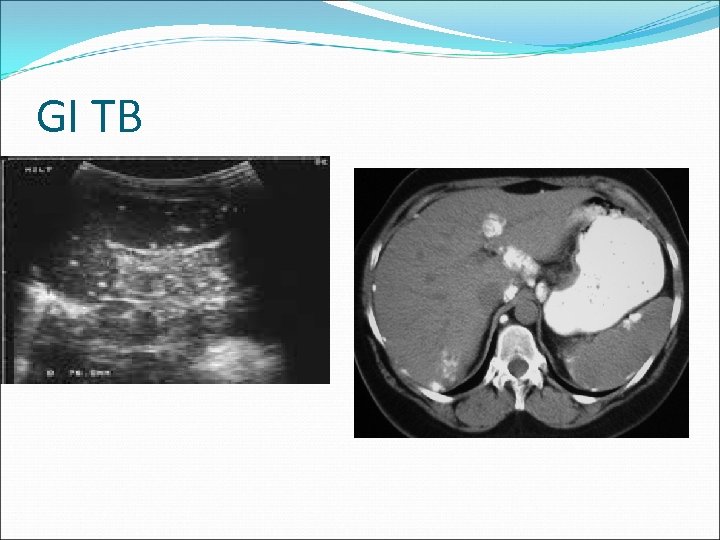

GI & GU Manifestations Abdominal/peritoneal TB Thickened gut, peritoneal lymph nodes Obstruction, fistula formation, ascitis, perforation, malapsorption Palpation doughy abdomen w/ masses of adherent lymph nodes R/o malignancy (laparoscopic biopsy) Poor prognosis, long term intestinal problems Renal TB Uncommon in children Sterile pyuria TB epididymitis and orchitis

GI TB